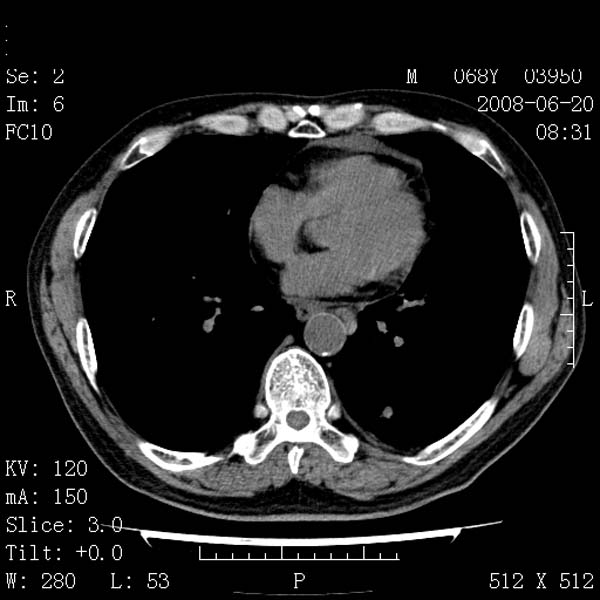

以下是引用zjzjr在2008-6-24 11:19:00的发言:[br]支持左下肺周围型肺癌伴右肺转移,纵隔淋巴结转移,心包积液.

以下是引用zhangling在2008-6-24 14:56:00的发言:[br]我们科室意见报告为[br][br]1考虑左下肺周围型肺癌[br]2右肺小结节考虑转移瘤,纵隔淋巴结转移[br]3心包积液. [br] 各位老师分析的相当好 谢意[br]